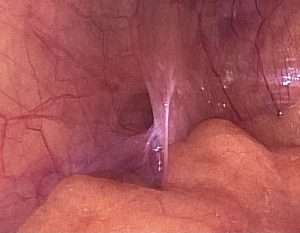

• Foto 1 y 2 anillo inguinal interno

Hernia inguinal izquierda vista por dentro de la cavidad abdominal

Herniaplastia inguinal laparoscópica transabdominal preperitoneal (técnica TAPP)